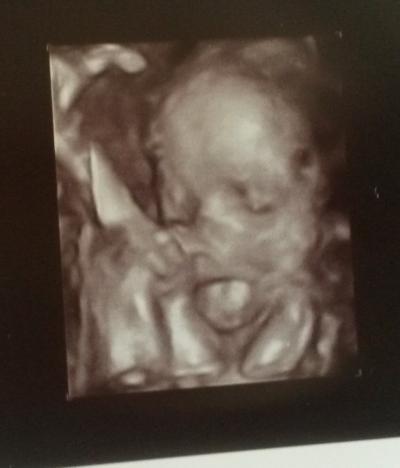

Ich liebe diese beiden... kann nicht aufhören die anzuschauen :) Bild 1 Zunge raus - echt ne lange Zunge!